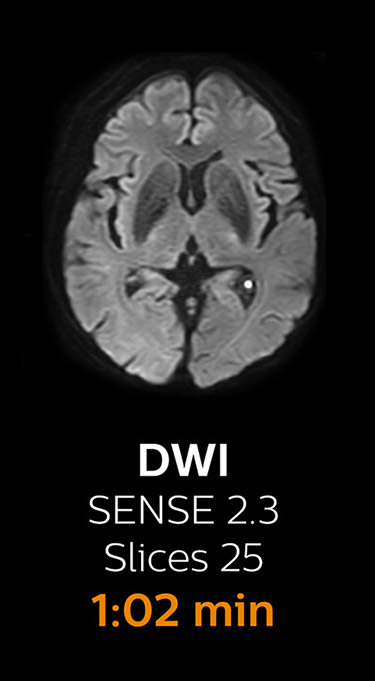

“We now only need about 10 minutes of scan time for a brain exam – and we still get the same amount of images and equal quality. We even managed to make a very useful improvement: we replaced the 43-second T2* FFE by a 43-second SWIp, which is more powerful for us in making confident diagnoses in certain patients.” “SWIp was not previously included in our standard protocol, because of its slightly longer scan time. SWIp provides high resolution 3D susceptibility weighted imaging in the brain, which helps to visualize small deoxygenated blood or calcium deposits. Now, with Compressed SENSE, we can perform 3D SWIp in only 43 seconds, so we have included SWIp instead of the 2D T2* FFE that we used previously. Without adding scan time, we now get SWIp images in every routine brain scan and it helps us increase our diagnostic confidence in certain cases.”

The most frequently used brain MRI examination at KNC included approximately 15 minutes of scanning time, and was quite comprehensive with fairly short scan times. When Compressed SENSE became available, its great impact on the brain exam quickly became clear.

Scanning time reduction in brain MRI with Compressed SENSE

With Compressed SENSE, the scan time for the routine brain examination at KNC was reduced from 15:48 to 10:19 minutes, which corresponds to 35% reduction.

Brain with Compressed SENSE

Ingenia 3.0T CX

Scan time 10:19 min.